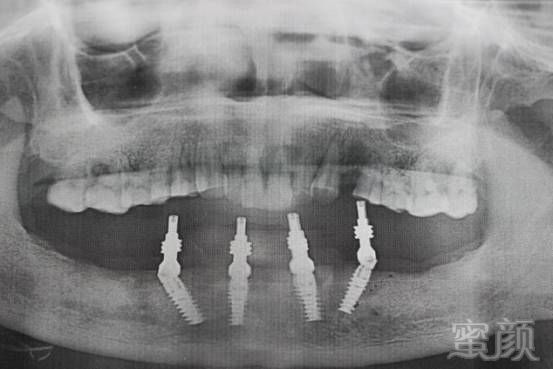

术后X影像↓↓

两侧植体成角度植入接入复合基台,避免损伤颏孔并能负荷后牙咬合力!